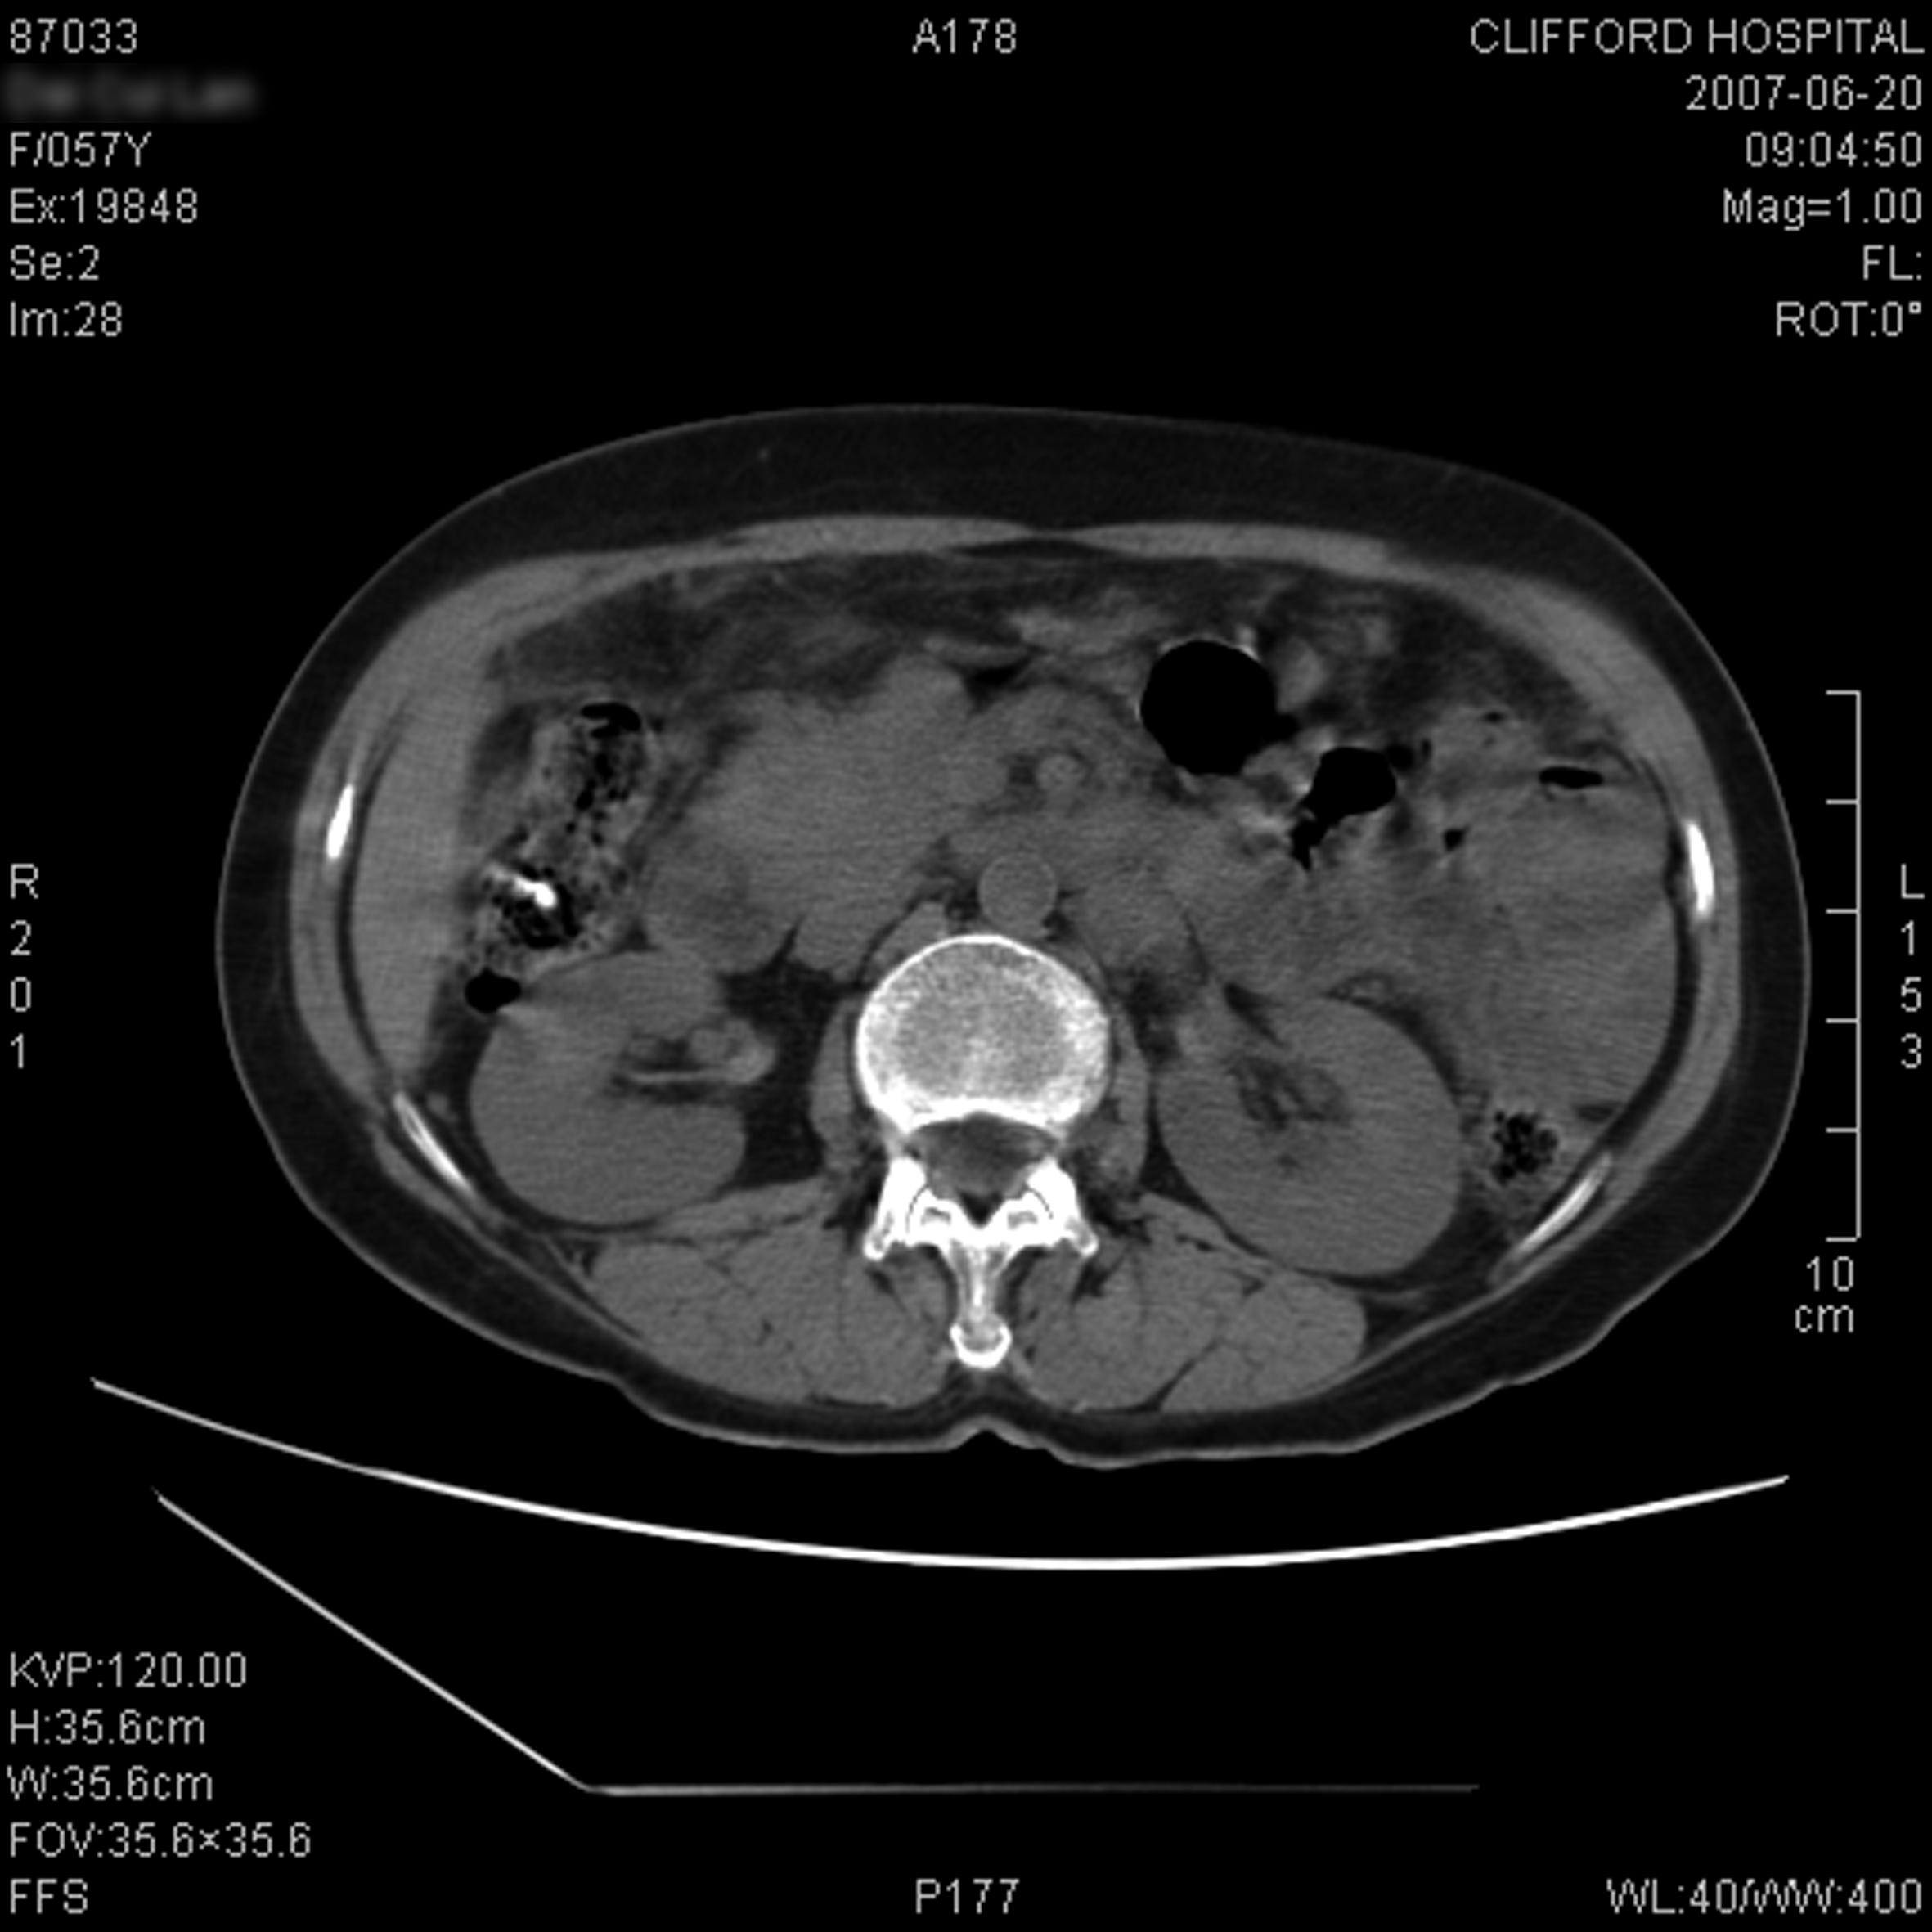

Typical Cases / Gastric Cancer__Clifford Hospital

Typical Cases / Gastric Cancer__Clifford Hospital